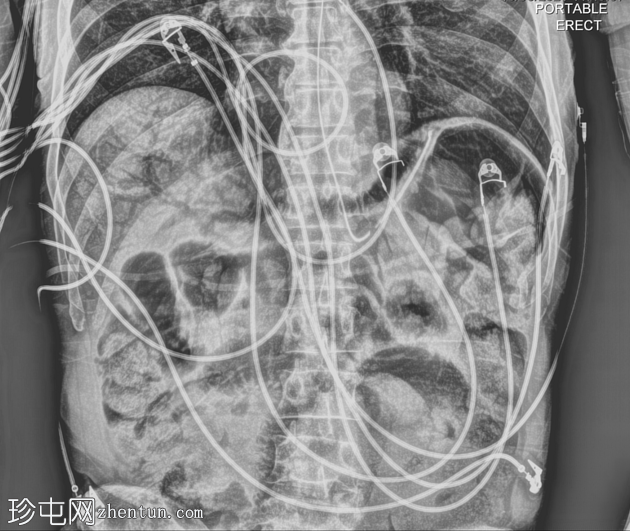

X线片

1.png

正位片